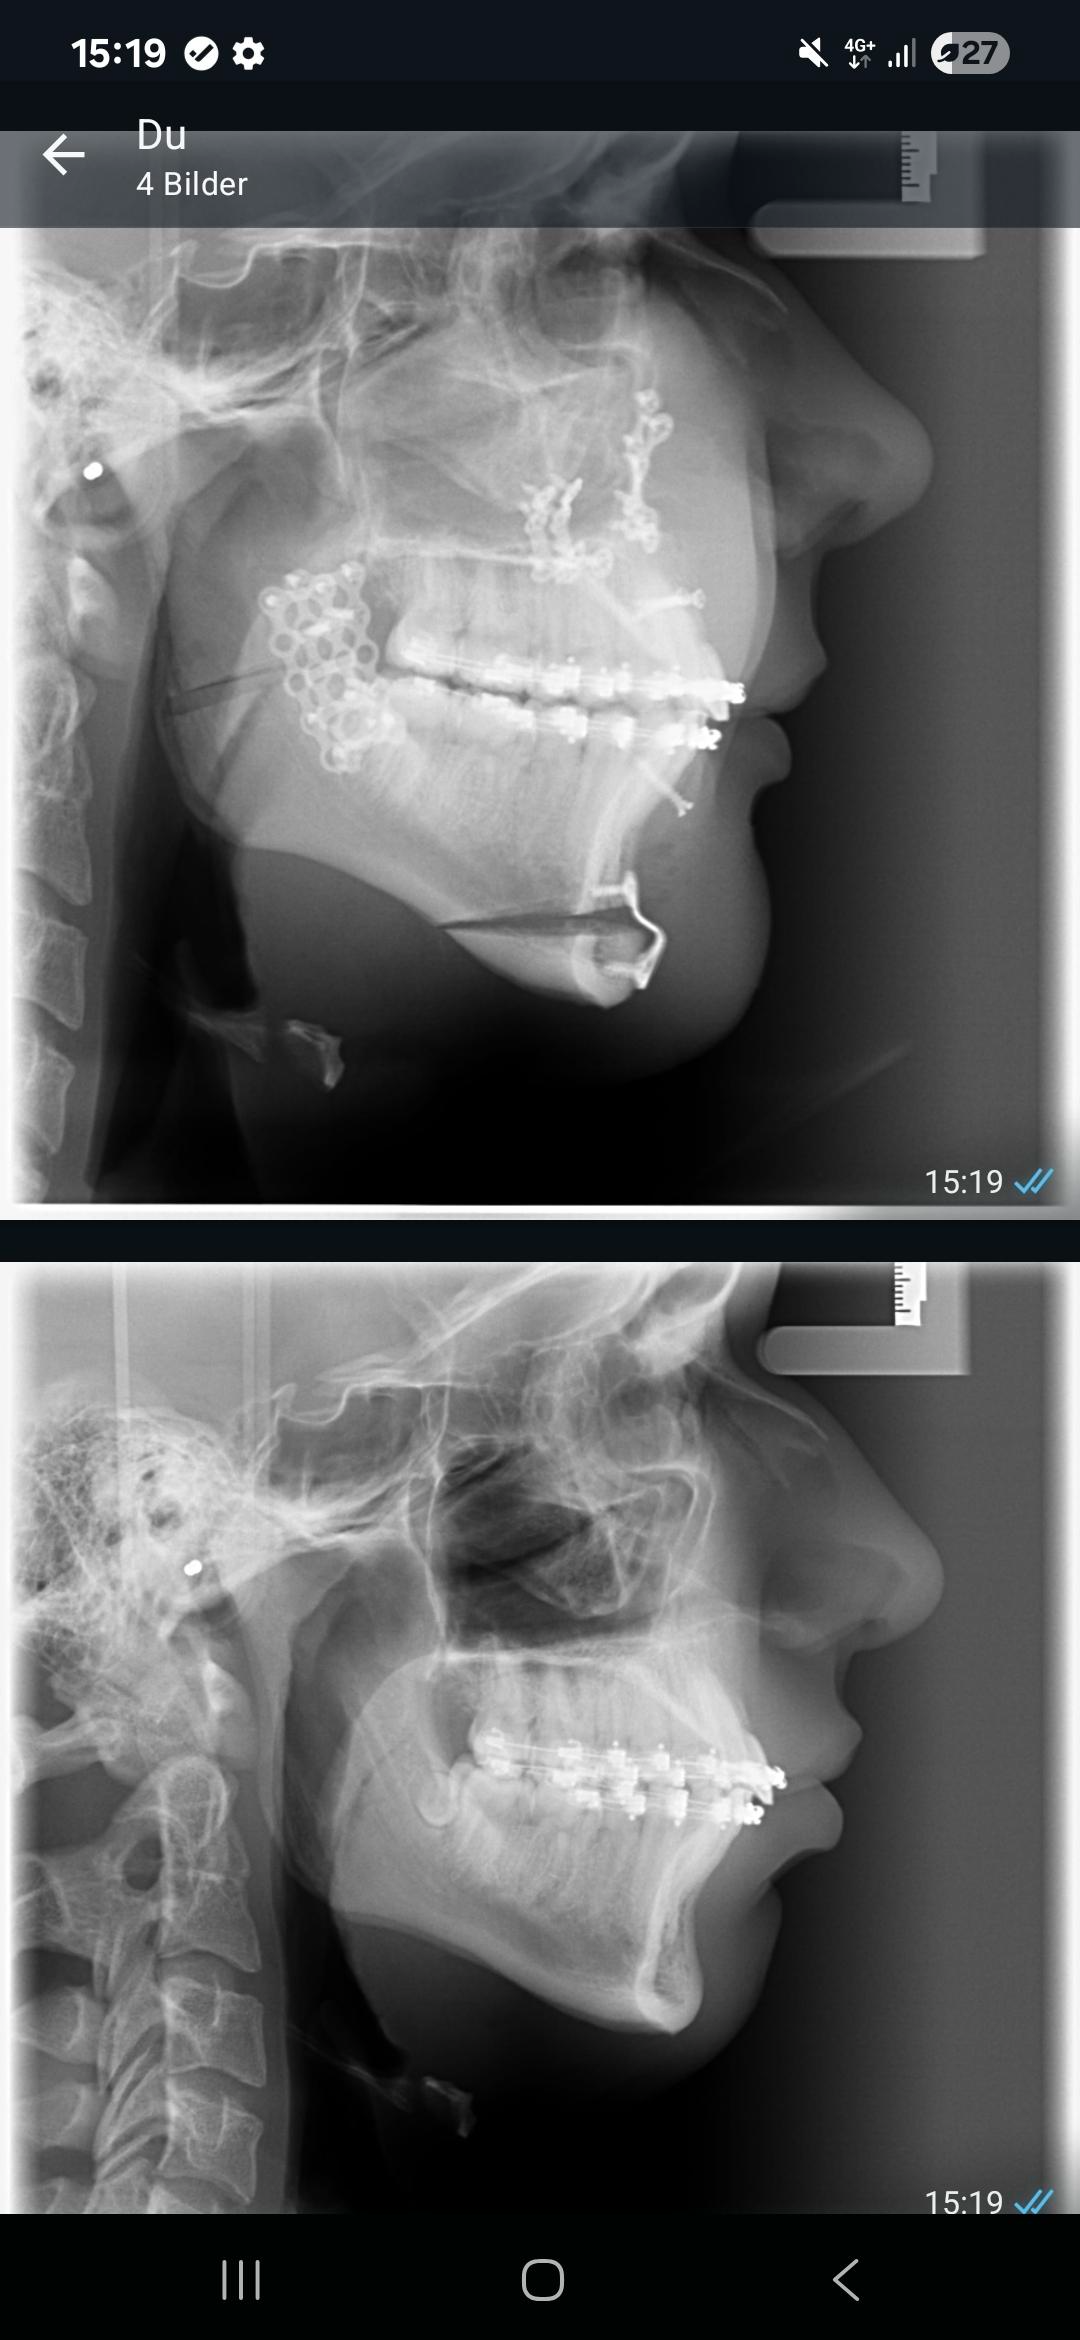

Rate my trimax

17 btw, cost 4.5K€

Before and after

I'm 4 weeks post surgery, so still pretty much swelling is left